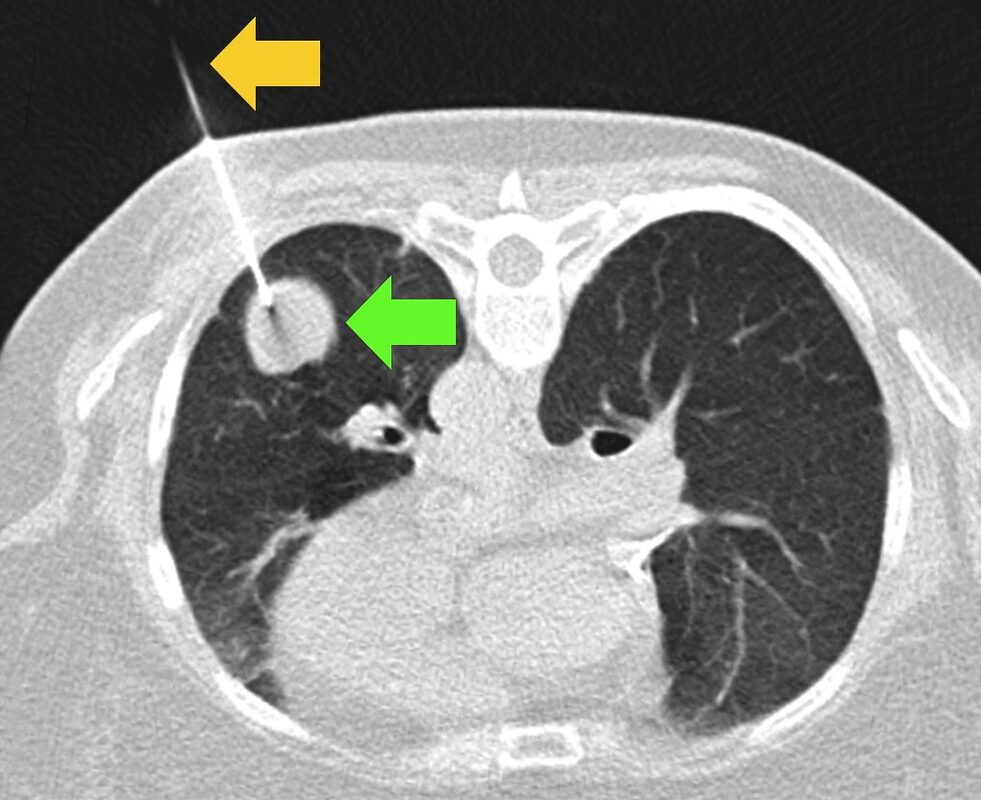

1. Phổi

Ung thư phổi đứng đầu về tỷ lệ tử vong toàn cầu. Theo báo cáo từ GlOBOCAN, có tới hơn 70% bệnh nhân ung thư phổi được chẩn đoán khi đã ở giai đoạn muộn (giai đoạn 3 hoặc 4).

Nguyên nhân là do cấu trúc phổi có nhiều ngóc ngách và bị các xương sườn che chắn nên phương pháp chụp X quang ngực thẳng thông thường rất khó phát hiện các nốt đơn độc có kích thước dưới 10mm. Những tổn thương nằm ở vị trí khuất thường chỉ được nhìn thấy rõ ràng qua chụp cắt lớp vi tính (CT) liều thấp, một kỹ thuật giúp giảm tỷ lệ tử vong do ung thư phổi tới 20% so với chụp X quang thông thường.